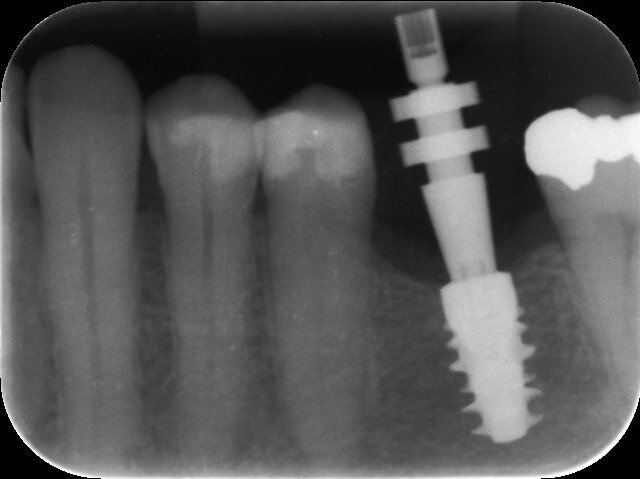

Fig. 9: Impression post engaged on to the implant correctly—no gap visible.

Fig. 10: Impression tray with impression post retained.